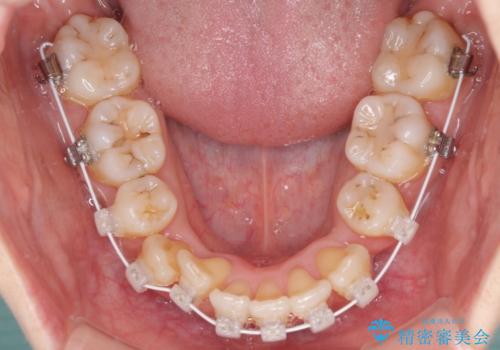

- 矯正装置

- 審美装置

- 結婚式に向けて、八重歯と虫歯で変色した歯を改善したいとのことで来院された患者様です。

上下ともにデコボコが強いため、上下顎左右小臼歯各1歯を抜歯して歯列を整えることとしました。

抜歯矯正は、2年半程度の治療期間を要することが一般的ですが、今回はセラミッククラウンによる補綴治療も含めて2年1ヶ月で終えることができました。